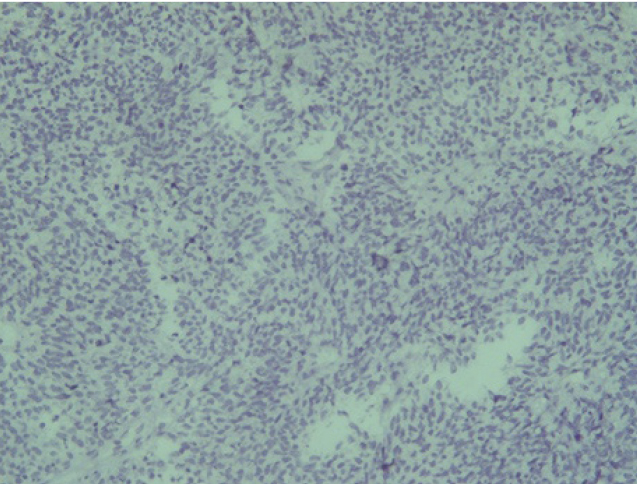

Отрицательная экспрессия была отмечена в диагностических образцах с использованием антител к Keratin.Pan, CD45, p63, S100, EMA (E29), TTF1(рис. 7–12).

Рис. 7. Keratin.Pan [AE/AE3] ×200

Рис. 8. CD 45 [Cocktail] ×200

Рис. 9. p63 [7JUL] RTU ×200

Рис. 10. S100 ×200

Рис. 11. EMA [E29] ×200

Рис. 12. TTF1 [8G7G3/1] ×200